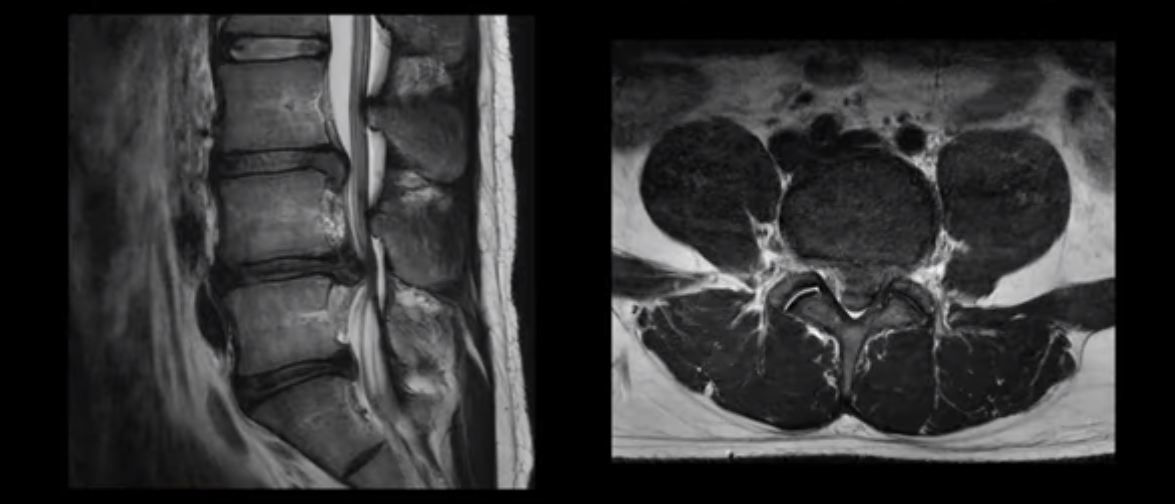

허리디스크 보존치료 좀 경험했다는 환자분들이 자기 경험으로 빗대어 방사통은 원래 오래 가는 것이 당연한 것처럼 말하는 경우가 많습니다. 그런데 저희 같은 비수술 척추치료를 전문적으로 10년 이상 수만 명씩 하고 있는 병원의 입장에서 보면 매우 답답하고 안타깝습니다. 그럼 이 4주 얘기가 파열이 심하지 않은 환자 얘기인지 궁금하실 텐데, 전혀 아닙니다. 여기 보는 MRI처럼 이 정도로 파열이 심하고, 심지어는 마비까지 있는 사람들의 이야기입니다. 이런 사람들이 최적화된 조건 하에서 평균 4주면 방사통이 가라앉는 것입니다.